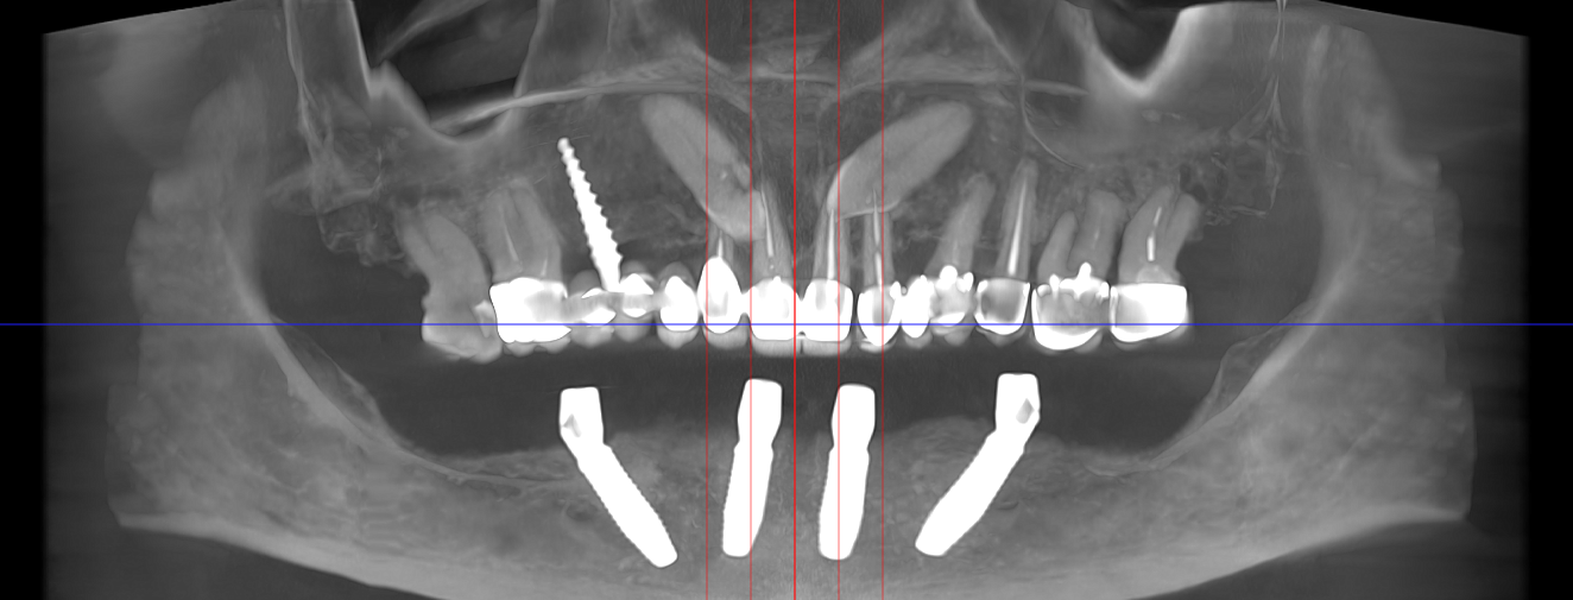

studii științifice.În cazurile de atrofie osoasă severă, când inserarea implanturilor în zonele laterale nu este posibilă fără adăugare osoasă, conceptul All-on-4 prevede plasarea implanturilor în unghiuri strategice pentru a evita zonele deficitare. Astfel, două implanturi sunt plasate în zona incisivilor laterali, iar alte două în zona premolarilor.

Tomografii (CBCT)

Caz 1